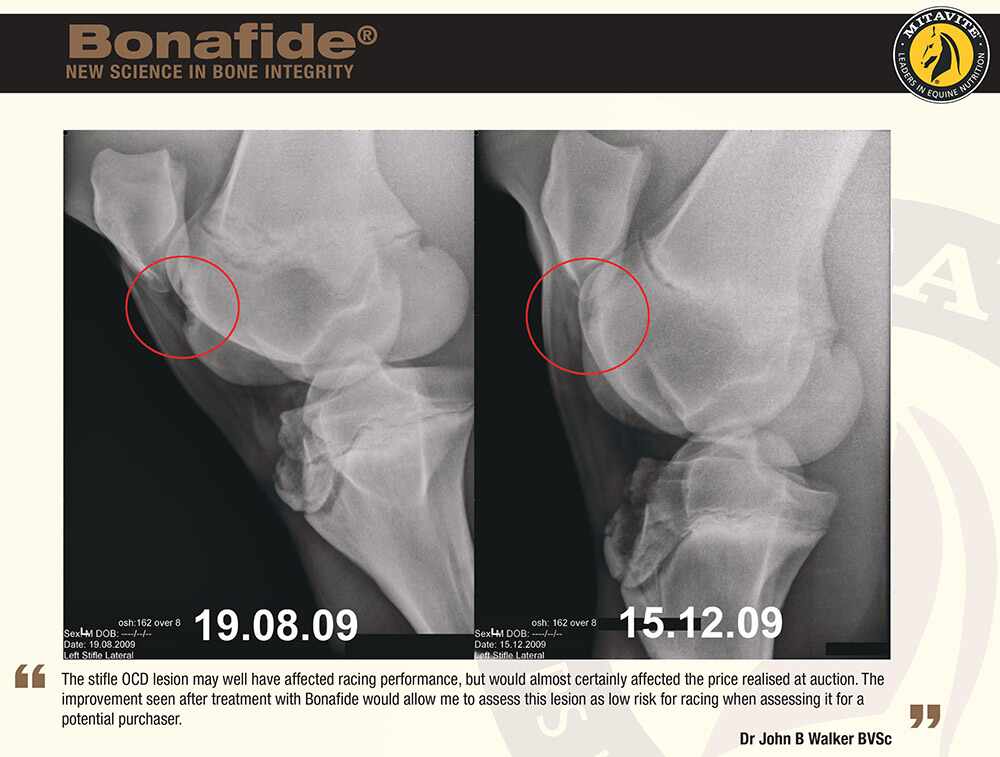

A study was conducted on presale thoroughbred yearlings, who were treated with 20g of Bonafide per day between the X-ray dates. The results showed marked improvement and in all cases eliminated the need for surgery.

A study was conducted on presale thoroughbred yearlings where X-rays were taken to identify those that might require surgery. The yearlings were treated with 20g of Bonafide per day between the X-ray dates. The results showed marked improvement and in all cases eliminated the need for surgery.